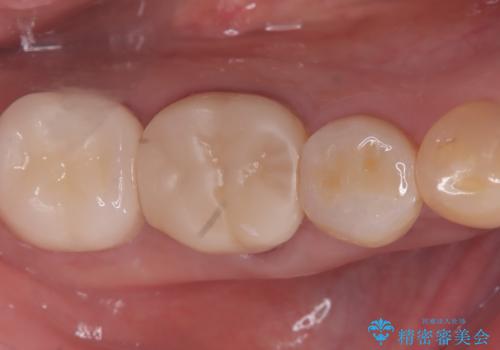

【セラミッククラウン】銀歯を白くしたい

- 主訴:笑った時に下の銀歯が目立つので、白いものに替えたい

失活歯に保険適応のメタルクラウンがセットされていました。

根尖病巣と根管内に破折ファイルを認め、ファイル除去は困難だということをお伝えし、根管治療・土台・クラウンのやり替えとなりました。

根管内破折ファイルの除去が難しいことから、近心根根尖部の洗浄が十分には行えない(病巣が消えない可能性がある)ことを了承いただき治療となりました。